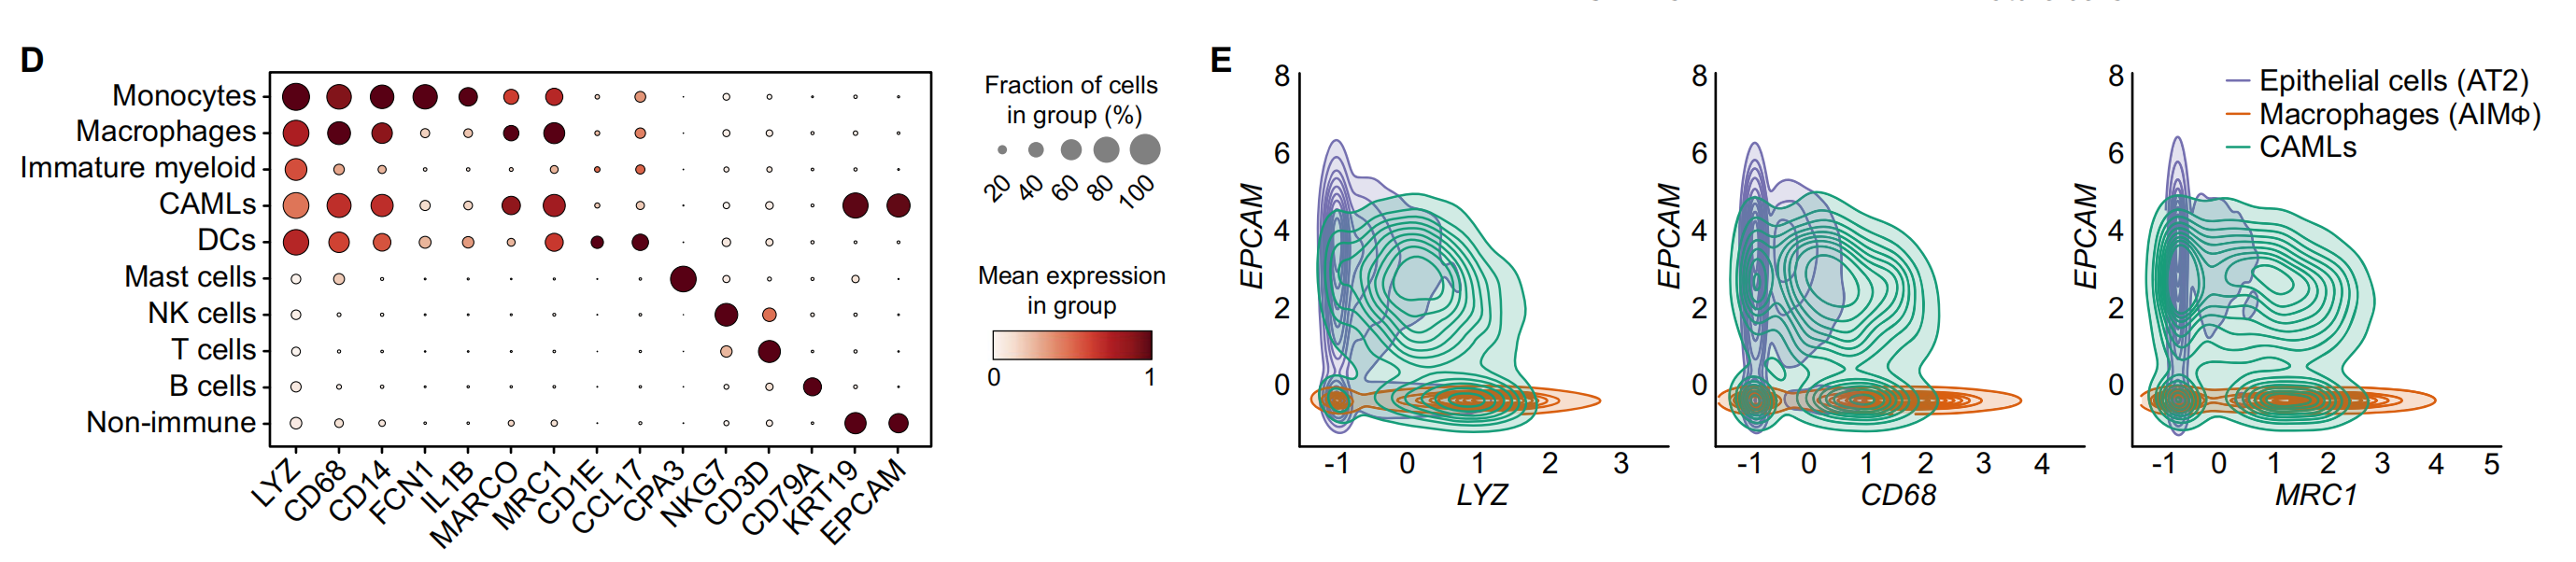

Fig. 1 展示了非小细胞肺癌(NSCLC)异质性的单细胞转录组学分析结果。

以下是对图中各个部分的分析:

A. 研究概述:从切除的肿瘤组织、邻近未受累组织(背景)以及已故捐赠者的健康肺中制备了单细胞悬浮液,并富集了CD45+或CD235-的细胞进行单细胞RNA测序(scRNA-seq)。使用新鲜冷冻的肿瘤、背景和健康组织的冷冻切片进行10x Genomics Visium空间转录组学研究。

B. 队列概览:符号代表了个体患者以及执行的分析。

C. UMAP投影:展示了肿瘤和结合背景+健康数据集的UMAP(Uniform Manifold Approximation and Projection)投影图,这是一种用于降维和数据可视化的技术。

D. 点图(Dotplot):显示了用于肿瘤样本中宽泛细胞类型注释的代表性基因。点图通常用于展示基因表达水平,点的大小代表表达量,颜色代表表达水平的变化。

E. 等高线图(Contour plot):展示了在AT2细胞(44,399个细胞)、CAMLs(2520个细胞)和AIMφ(16,120个细胞)中共表达的髓系(LYZ, CD68, MRC1)和上皮系(EPCAM)基因。这些数据被标准化、缩放和对数转换。

F. 箱线图(Boxplot):展示了在AT2细胞、CAMLs和AIMφ中髓系(LYZ, APOE, CD68, MRC1)和上皮系(EPCAM, KRT8, KRT19)基因的标准化、缩放和对数转换后的基因表达。箱形图显示了四分位数,须表示1.5倍四分位距。

G. 非免疫细胞亚群的相对比例:在CD235-富集中计算的肿瘤与背景之间的差异。箭头指示了肿瘤与背景相比的增加(↑)或减少(↓)。使用双边Wilcoxon秩和检验和Bonferroni校正进行多重比较。**P < 0.01。没有星号的箭头表示该细胞类型仅在肿瘤或背景中发现。

H. 广泛免疫细胞的相对比例:在所有免疫细胞中识别的CD235-富集中计算的肿瘤与背景之间的差异。箭头指示了肿瘤与背景相比的增加(↑)或减少(↓)。使用双边Wilcoxon秩和检验和Bonferroni校正进行多重比较。*P < 0.05, **P < 0.01, ***P < 0.001。没有星号的箭头表示该细胞类型仅在肿瘤或背景中发现。

I. 肿瘤和背景中NK、DC、B、T细胞和巨噬细胞亚群的相对比例:在CD235-富集中计算的广泛注释内的肿瘤与背景之间的差异。箭头指示了肿瘤与背景相比的增加(↑)或减少(↓)。使用双边Wilcoxon秩和检验和Bonferroni校正进行多重比较。***P < 0.001。没有星号的箭头表示该细胞类型仅在肿瘤或背景中发现。

总体而言,Fig. 1 通过单细胞转录组学和空间转录组学技术,揭示了肿瘤组织与邻近正常组织在不同细胞类型上的异质性和差异。这些结果有助于深入理解肿瘤微环境中细胞的复杂性,并为未来的治疗策略提供潜在的靶点。